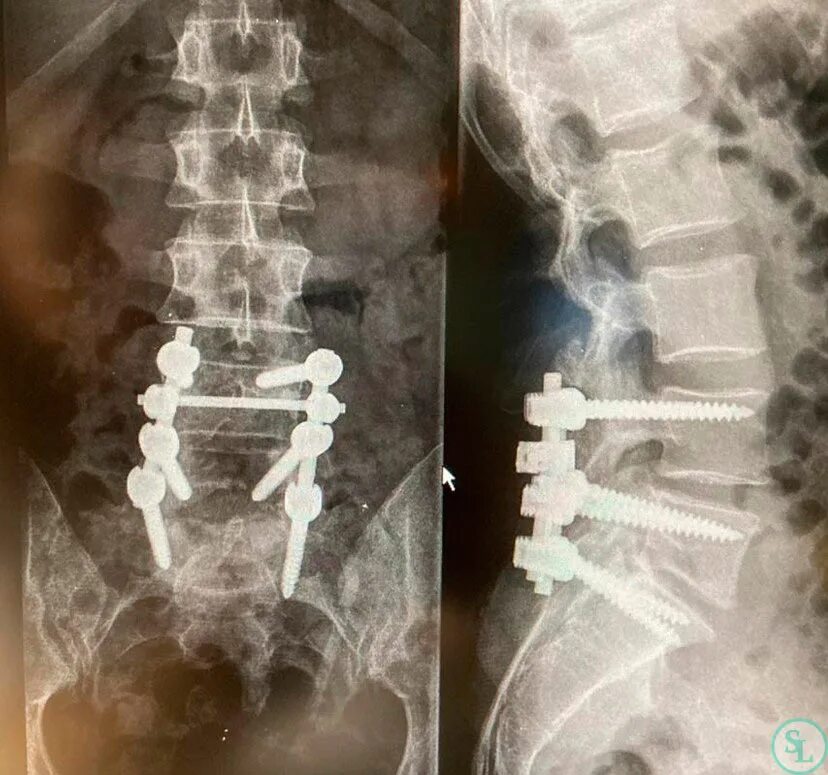

Диффузная грыжа l4 l5